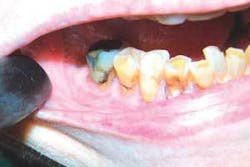

Upon examination, I noted exposure of the mandible on the lingual running from Teeth Nos. 18 and 19. At that time there was no information available to suggest treatment of this problem, and the patient and I agreed to monitor the situation.

The patient was seen for prophylaxis every six months between 2004 and 2006. Occasionally the patient reported abscess and pain on the lower right molar area. Alternating antibiotics eliminated this pain until May 2006, when the patient’s husband reported that the infection was not responding to antibiotic therapy. The patient had limited opening of the mouth and could not eat.

She was immediately referred to an oral surgeon. Upon examination he discovered mandibular necrosis around Tooth No. 31. The situation had become life-threatening, as the infection was now out of control and spreading through the soft tissue, floor of the mouth, and buccal space.